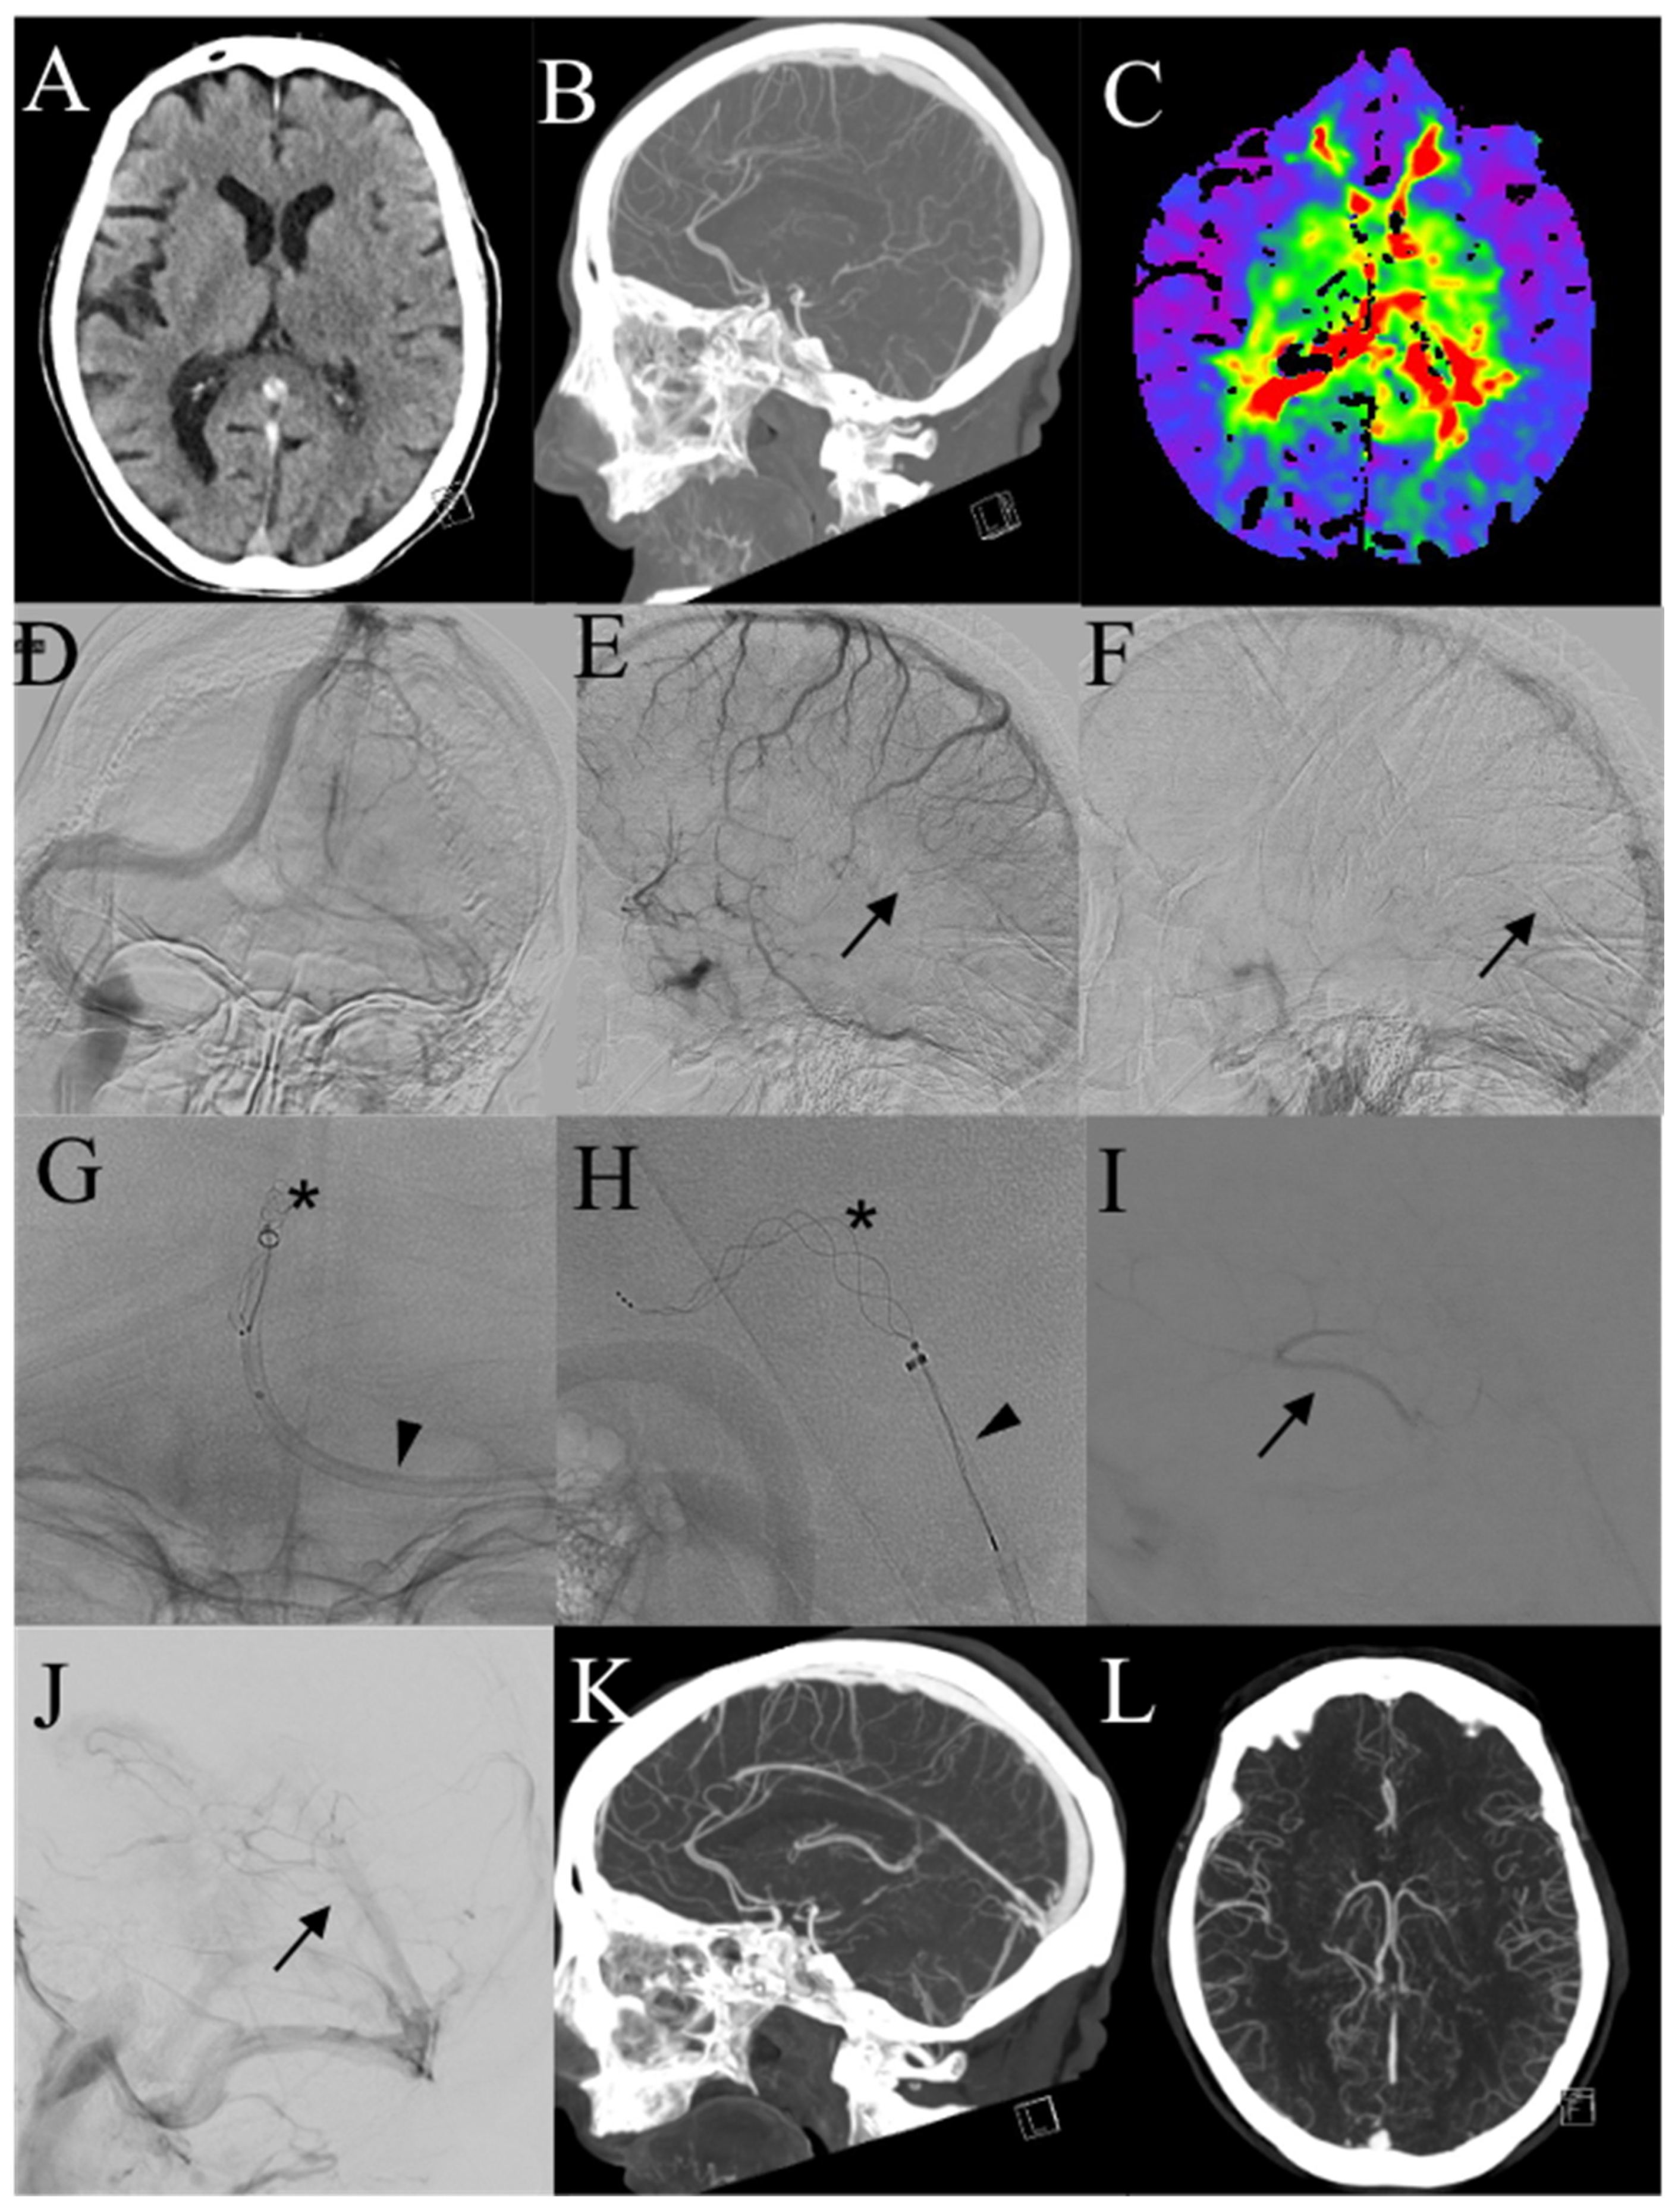

| 1 | F, 72 | Headache, nausea, aphasia, rt hemisyndrome | No identifiable risk | SSS, SS, SrS, TS, VG | SAH | 7 h | Rescue | Combined Aspiration plus Stentriever |

| 2 | F, 84 | Headache, aphasia, rt hemisyndrome | No identifiable risk | TS, ICV, VG, TS, SS | No | 5 h | Primary | Combined Aspiration plus Stentriever |

| 3 | M, 52 | Headache, nausea, dizziness | Antiphospholipid antibodies + | TS | IPH, SAH | 6 h | Primary | Aspiration |

| 4 | F, 51 | Headache, rt hemisyndrome, seizures | Contraceptive pill, MTHFR mutation | SSS | IPH, SAH | 2 h | Primary | Aspiration |

| 5 | F, 40 | Headache, aphasia, seizures | Antithrombine III and Protein S deficiency, contraceptive pill | TS, SS, JV | IPH | 7 h | Rescue | Aspiration |

| 6 | F, 44 | Headache, lt hemisyndrome, seizures | No identifiable risk | SSS | SAH | 1 h | Rescue | Aspiration |

| 7 | M, 41 | Headache, nausea, photophobia, lt sup. arm deficit | ANA+ | SSS | IPH | 2 h | Primary | Combined Aspiration plus Stentriever |

| 8 | F, 44 | Headache, aphasia | Contraceptive pill, activate protein C resistance | TS, SS | SAH | 4 h | Primary | Aspiration |

| 9 | F, 76 | Headache, seizures, loss of consciousness | No identifiable risk | SSS, SrS, TS (both), SS | No | 5 h | Primary | Aspiration |

| 10 | F, 33 | Headache, nausea, lt hemisyndrome | Pregnancy | SSS, SrS, TS (both), SS (both) | No | 2 h | Primary | Combined Aspiration plus Stentriever |

| 11 | F, 49 | Headache, vomiting, dizziness, aphasia, rt hemisyndrome | Recent pulmonary embolism | SSS, TS (both), SrS, | IPH, SAH | 2 h | Primary | Combined Aspiration plus Stentriever |

| 12 | F, 49 | Headache, nausea, dizziness, lt sup. arm deficit | Contraceptive pill, C677T and A1298C MTHFR mutation | Panthrombosis | No | 2 h | Primary | Aspiration |

| 13 | F, 45 | Headache | No identifiable risk | TS, SS | SAH | 6 h | Primary | Aspiration |

| 14 | F, 44 | Headache, nausea, aphasia, rt hemisyndrome | Contraceptive pill | TS | IPH | 3 h | Primary | Combined Aspiration plus Stentriever |

| 15 | M, 83 | Aphasia, rt hemisyndrome | Progestogen therapy | SSS, TS, SS, JV | IPH | 24 h | Rescue | Combined Aspiration plus Stentriever |

| 16 | M, 49 | GCS 9 | Neurosurgery 9 days prior | SSS, TS | No | 5 days | Rescue | Aspiration |

| 17 | F, 16 | Headache, nausea | Previous contralateral CVT, Prothrombin gene mutation | SSS, TS, SS | No | 2 h | Primary | Aspiration |

| 18 | F, 40 | Headache, nausea, rt hemiparesis | Prothrombin gene mutation (A20210G homozygosis) | SSS, SrS, TS (both), SS | IPH | 48 h | Rescue | Aspiration |

| 19 | F, 27 | Headache, nausea, dizziness, lt hemisyndrome | Contraceptive pill | SSS, rt parietal vein | IPH | 48 h | Rescue | Combined Aspiration plus Stentriever |

| 20 | F, 27 | Headache, nausea, rt hemisyndrome | Thalassemia | SSS, lt temporal vein | IPH | 48 h | Rescue | Combined Aspiration plus Stentriever |

| 21 | M, 19 | Headache, nausea, vomiting, dizziness | Active protein C resistance, MTHFR mutation | TS, SS | IPH, SAH | 3 h | Primary | Aspiration |